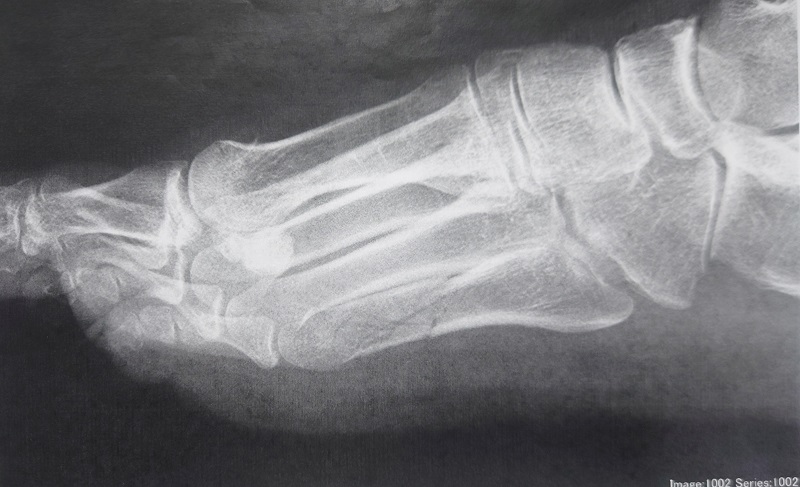

右第5中足骨粉砕骨折(80代女性)の施術一例